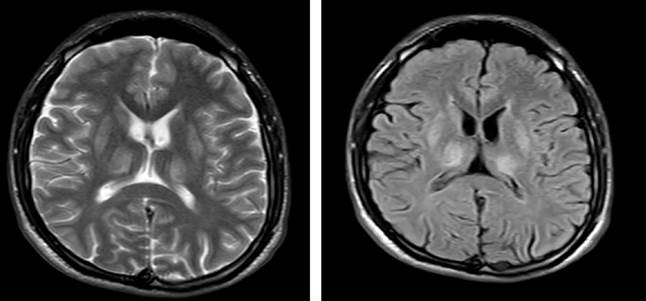

Two months before admission, the patient developed progressive lower limb weakness, gait disturbances with an increased base of support, and incoordination of gross and fine motor activities. He also exhibited bradylalia, which progressed to mild dysarthria, dysphagia for solids and liquids, and sialorrhea. Subsequently, he experienced a tonic posturing episode involving flexion of the upper limbs, extension of the lower limbs, and retrocollis lasting one minute, with preserved consciousness and no sphincter relaxation or tongue biting. A non-contrast brain MRI revealed thalamic and lenticular nucleus lesions, hypointense on T1 and hyperintense on T2 and fluid-attenuated inversion recovery (FLAIR) sequences, with no additional abnormalities (Figure 1). Two electroencephalograms, one 6-hour and another 12-hour, showed no ictal activity. During clinical evolution, the patient displayed impaired attention (dysexecutive symptoms), recurrent overvalued anxious thoughts, and a labile and anxious mood, with intact memory, preserved sleep, and appetite.

In magnetic resonance imaging (MRI), early abnormalities are often non-specific but can be valuable for diagnosing unexplained neurological or psychiatric symptoms. Findings may include alterations in the basal ganglia, thalami, pons, and white matter. Data show evidence of cerebral atrophy, bilateral symmetrical lesions in the caudate and putamen (characterized by concentric laminar increases in T2 signal intensity), and T2 signal hyperintensities in the substantia nigra (pars compacta), periaqueductal gray matter, pontine tegmentum, and thalamus. Additionally, T2 signal hyperintensities may be observed in the periaqueductal gray matter, substantia nigra, and around the red nuclei, which maintain their normal hypointensity. A late-stage hallmark, the panda sign, consists of T2 hyperintensity in the midbrain and has been considered pathognomonic. However, similar changes may be seen in chronic liver disease, which must be taken into account. It is clear that MRI is not useful for determining prognosis or monitoring neurological symptoms3,5. In the present case, the disease onset was less than 12 months, and hyperintensity in the basal ganglia was documented without evidence of the panda sign, suggesting a rapidly progressive course driven by neurological involvement.